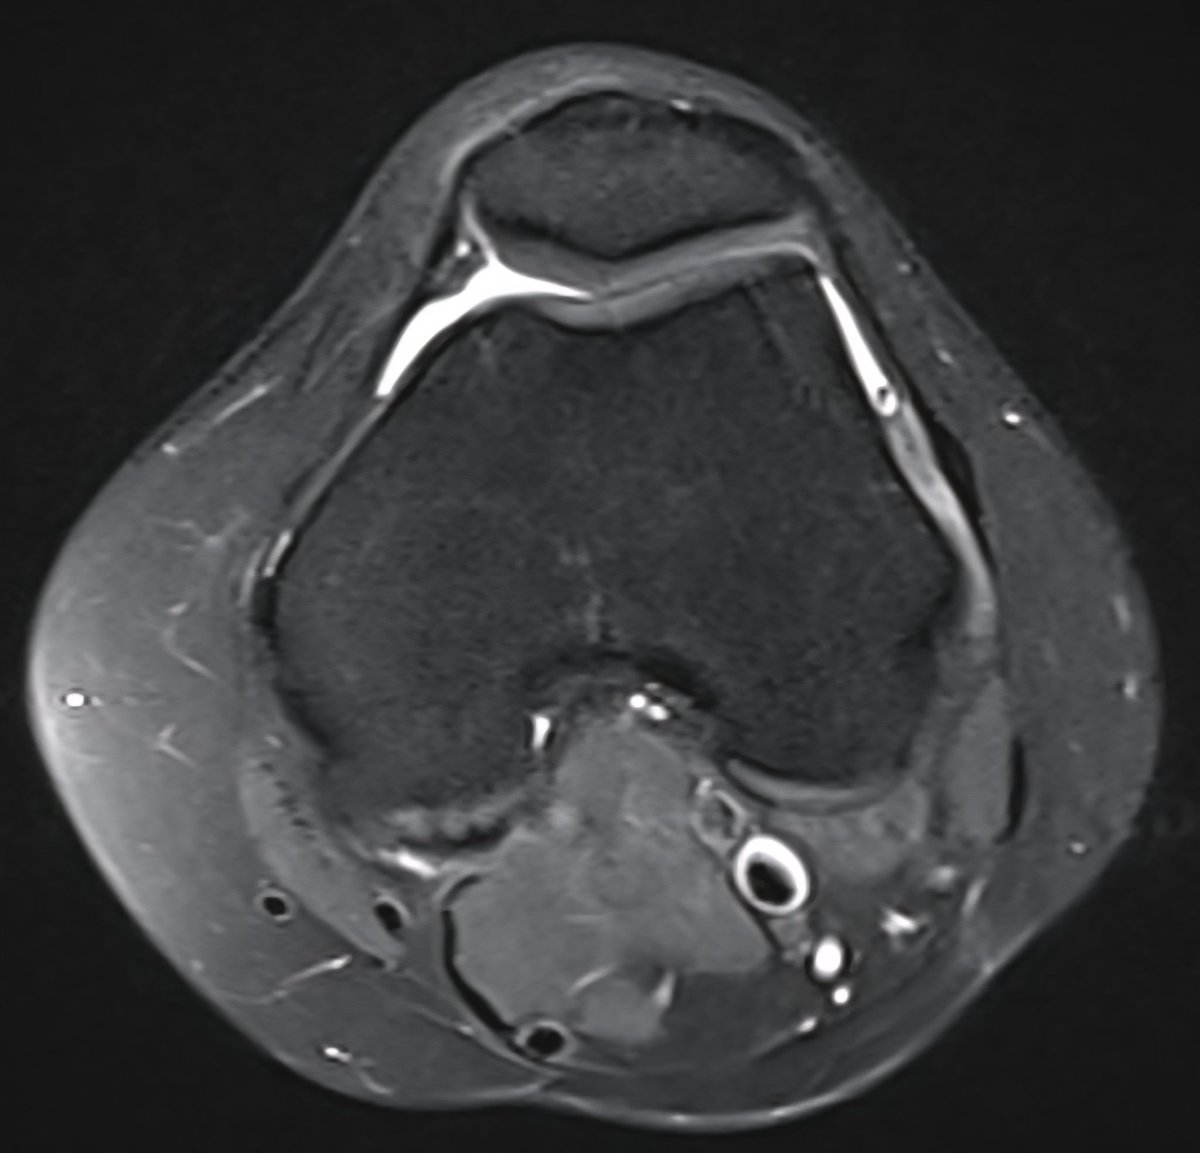

Consent ✅ Right hip pain & stiffness Both hip joints show OA changes - but R more advanced than L Why?